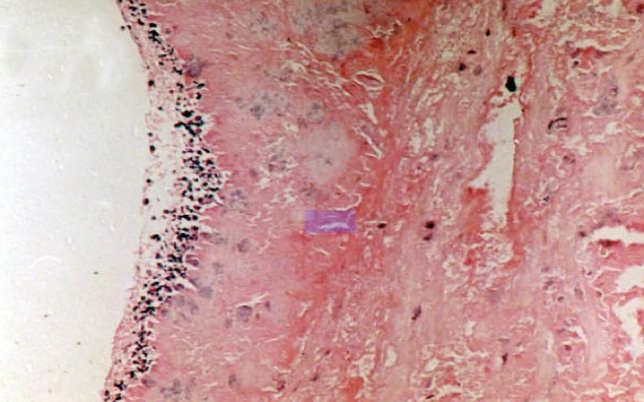

图2-1

镜下,赘生物由血小板、纤维素、坏死组织、炎细胞、细菌菌落构成。细菌菌落包裹在赘生物内部。溃疡底部可见少许肉芽组织及淋巴细胞、单核细胞浸润。有时可见原有风湿性心内膜炎的病变。